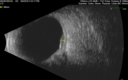

61 year old man with amelanotic choroidal nevus. Vision Normal - Stable over 4 years.

Amelanotic Choroidal Nevus - Multimodal Imaging577 views61 year old man with amelanotic choroidal nevus. Vision Normal - Stable over 4 years.00000